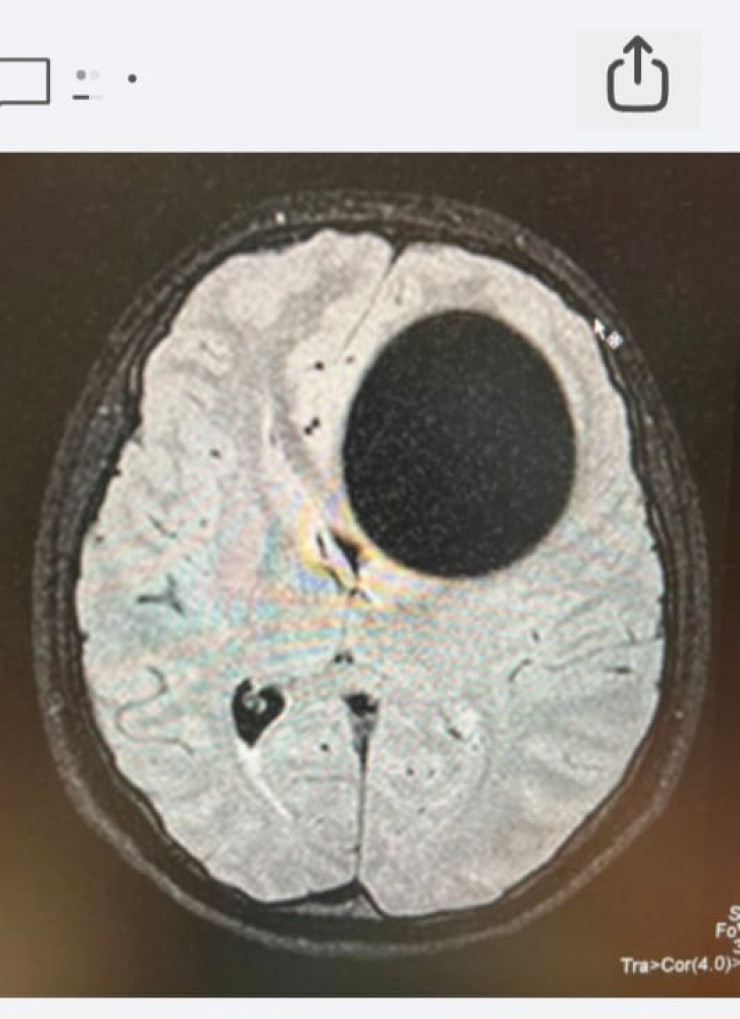

Накануне нейрохирурги Семея извлекли гигантскую эхинококковую кисту из головы пациентки. 20-летняя девушка поступила 17 января к невропатологам больницы скорой медицинской помощи (БСМП) Семея. Сначала у нее подозревали инсульт, однако на компьютерной томографии в головном мозге была выявлена огромная киста диаметром 5,5 сантиметра.

КТ-снимок до операции.